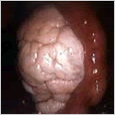

女性内生殖系统图